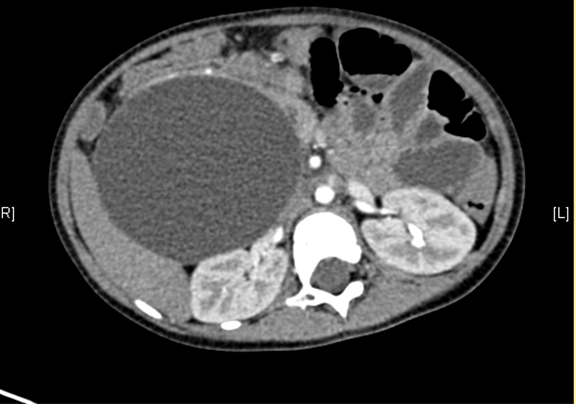

术前CT检查:

动脉期

上腹部增强CT:考虑先天性胆管扩张症(胆总管明显)。

将0.625mm双源薄层CT资料的静脉期和动脉期Dicom格式文件导入海信CAS系统。

通过调节窗宽窗位调整CT序号,对肝实质,胆囊,胆总管,下腔静脉,肝动脉、门静脉及肝静脉等进行三维重建;系统自动计算肝脏体积。